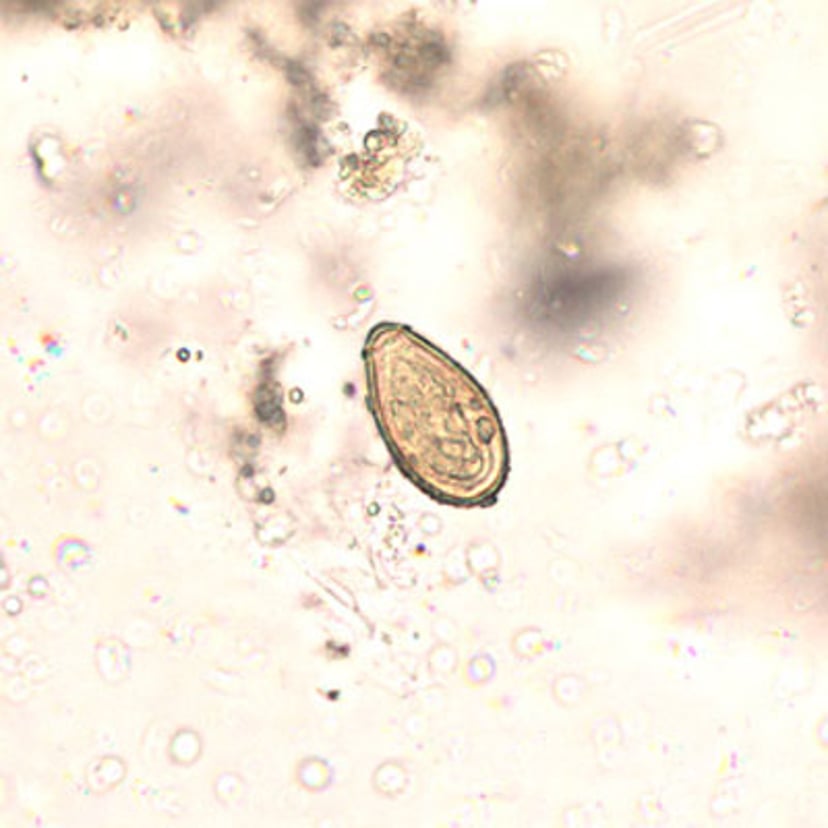

后睾吸虫

卵

后睾吸虫属

虫卵长19至30微米,宽10至20微米。它们通常与

华支睾吸虫

卵难以区分。

虫卵具有卵盖,卵盖肩部明显,并有一个反卵盖结节。虫卵随粪便排出时已形成胚胎。

CDC/DPDx